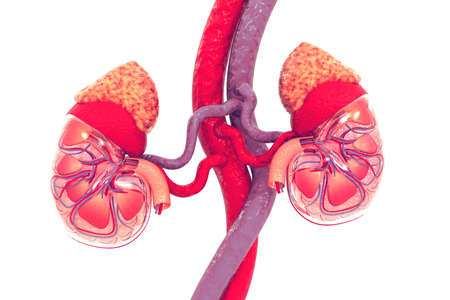

3 d illustration of human kidneys anatomy (human organs)